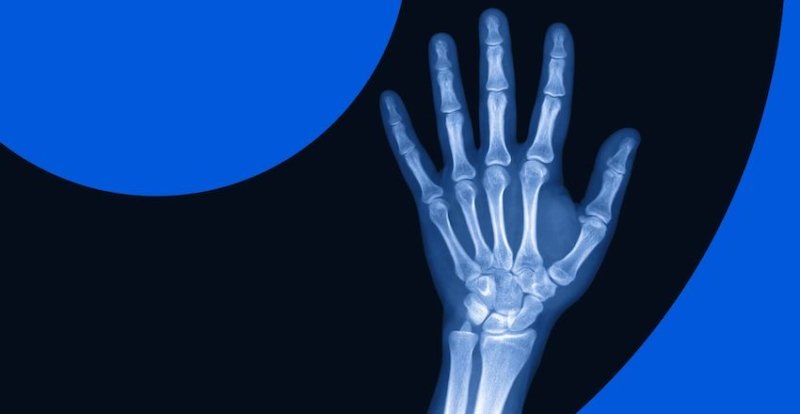

Рентген — преимущества, как проводится и когда назначается

Рентген является неинвазивным исследованием в медицине, которое позволяет создать проекцию анатомических структур. Этот вид исследований широко применяется и остаётся одним из наиболее распространенных. Использование рентгенографии актуально благодаря высокой информативности. Универсальность метода позволяет получить представление о состоянии организма и поставить высокоточный диагноз. Пройти рентген в Одессе можно в клинике «Амбулатория семейного доктора».

- переломы костей;

- вывихи суставов;

- при воспалениях, аномалиях и пороках роста костей, позвоночника и суставов;

- при дегенеративно-дистрофических изменениях частей скелета;

- кости и суставы;